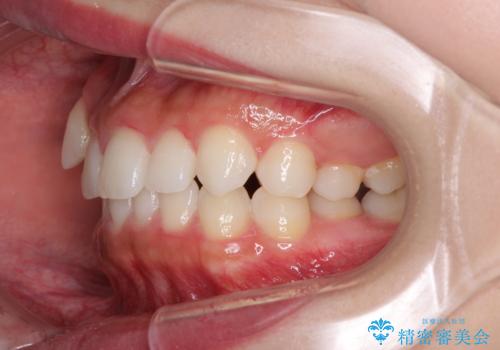

- 八重歯を気にして来院された患者様です。

本来であれば八重歯の隣後方の歯を抜歯するのですが、その後ろの歯が乳歯であり後続永久歯もなかったため、乳歯を抜去することとしました。

前から5番目の乳歯は、後続永久歯である小臼歯と比べて幅径が大きいため、移動に時間がかかりましたが、きれいに仕上げることができました。